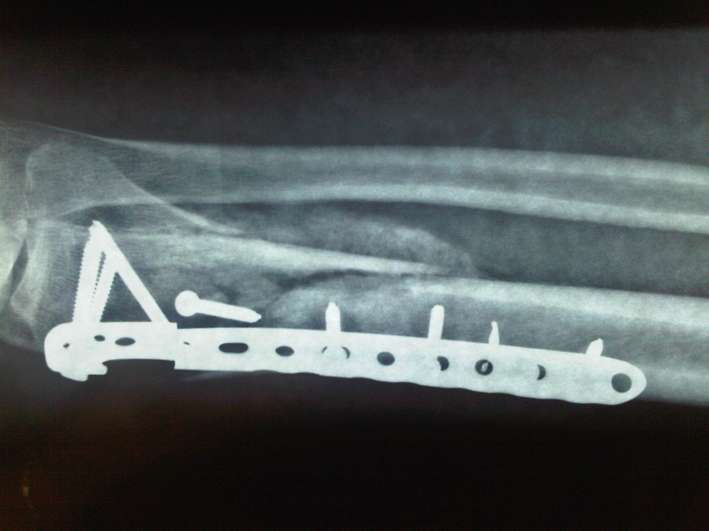

Seconda operazione: rimozione placca rotta e "montaggio" nuova placca:

Nuova placca